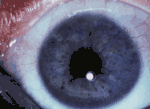

Узелки Лиша

Узелки Лиша встречаются практически у всех больных нейрофиброматозом I типа старше 20 лет. Они представляют небольшие белесоватые пятна (гамартомы) на радужке глаза. Узелки Лиша не видны невооружённым взглядом, необходимо офтальмологическое обследование. Выявляемость узелков Лиша повышается с возрастом больного: в возрасте от 0 до 4 лет — до 22 % случаев; 5—9 лет — до 41; 10—19 лет — до 85 %; старше 20 лет — до 95 % больных нейрофиброматозом I типа[24]. Данные узелки не встречаются при других формах нейрофиброматоза[37].

Впервые гамартомы радужной оболочки были описаны в 1918 году[38]. Их значение в диагностике нейрофиброматоза I типа было показано в 1937 году австрийским офтальмологом Карлом Лишем, в честь которого они и получили своё название. Впоследствии была установлена их чрезвычайная роль в дифференциальной диагностике болезни Реклингхаузена[39][40].